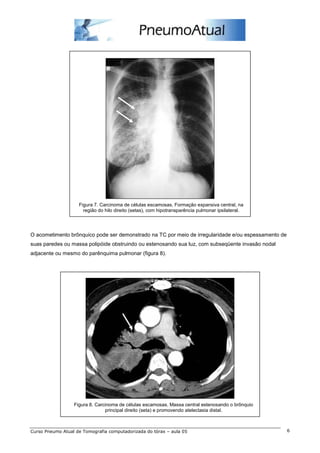

Nos métodos de imagem comumente exibe localização central, mantendo relação com o brônquio principal,

lobar ou segmentar em até dois terços dos casos (figura 7).

Figura 7. Carcinoma de células escamosas. Formação expansiva central, na

região do hilo direito (setas), com hipotransparência pulmonar ipsilateral.

O acometimento brônquico pode ser demonstrado na TC por meio de irregularidade e/ou espessamento de

suas paredes ou massa polipóide obstruindo ou estenosando sua luz, com subseqüente invasão nodal

adjacente ou mesmo do parênquima pulmonar (figura 8).

Figura 8. Carcinoma de células escamosas. Massa central estenosando o brônquio

principal direito (seta) e promovendo atelectasia distal.